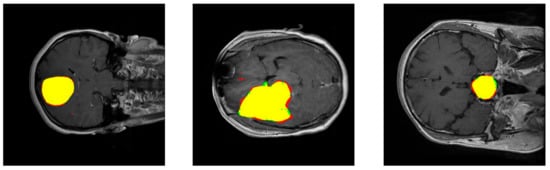

The aim of the work presented in this paper is to develop and test a Deep Learning approach for brain tumor classification and segmentation using a Multiscale Convolutional Neural Network. To train and test the proposed neural model, a T1-CE MRI image dataset from 233 patients, including meningiomas, gliomas, and pituitary tumors in the common views (sagittal, coronal, and axial), has been used [5]. Figure 1 shows examples of these three types of tumors. Additional information on the dataset is included in Section 2.2. Our model is able to segment and predict the pathological type of the three kinds of brain tumors, outperforming previous studies using the same dataset.

Figure 1.

Examples of MRI images of the T1-CE MRI image dataset. Left: coronal view of a meningioma tumor. Center: Axial view of a glioma tumor. Right: sagittal view of a pituitary tumor. Tumor borders have been highlighted in red.

This dataset contains 3064 slices and includes meningiomas (708 slices), gliomas (1426 slices), and pituitary tumors (930 slices) in the common views (sagittal, coronal, and axial). Figure 1 shows examples of these three types of tumors. This dataset provides also 5-fold cross-validation indices. By using this information, 80% (2452) of the images are employed for training and 20% (612 images) are used for obtaining performance measurements. The process is repeated 5 times.